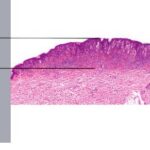

Unlike ordinary nevi and melanomas, melanocytic cells in Spitz nevi are large—often twice the size of epidermal basal keratinocytes, with prominent mononuclear or multinucleated giant cells in the epidermis and/or dermis . Mitoses, usually few in number, are detected in one-half the cases, whereas atypical mitoses are uncommon in Spitz nevi. In contrast to melanoma, the melanocytic cells in Spitz nevi show progressive maturation with increasing depth, becoming smaller and more similar to ordinary nevomelanocytes, with the overall distribution of cells in the dermis being wedge-shaped, with narrowing of the wedge toward the subcutaneous fat.

Melanocytic elements are usually arranged in well-circumscribed nests, although there may be permeation of the epidermis by single cells or small groups of cells. In those cases with epidermal nests, artifactual clefts are usually seen above the nests in half the cases, a finding rarely observed in melanoma. The epidermis is usually hyperplastic, with elongated and bulbous pegs and knobs extending into the dermis, although thinning and even ulceration may occur rarely. The dermal inflammatory cell infiltrate may be slight or marked, band-like, and mainly at the base or patchy around blood vessels and/or intermixing with tumor cells. Although melanin was observed in all 13 patients originally described by Spitz, more recent studies have determined that melanin was moderate in 10 percent of cases and heavy in 5 percent.88